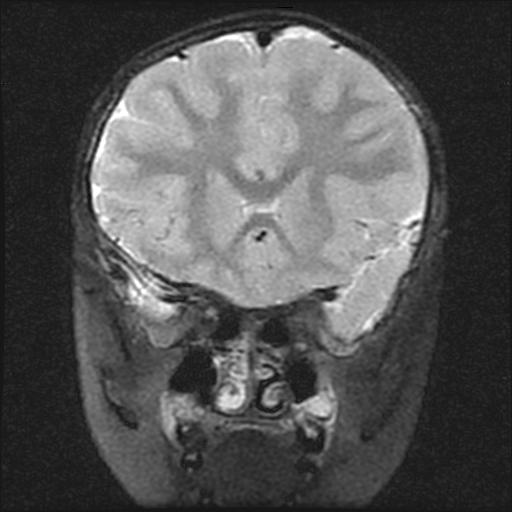

标题: PED0377: 6岁小儿,左侧视神经瘤术后 [打印本页]

6岁小儿,左侧视神经瘤术后。现左侧视力减退。